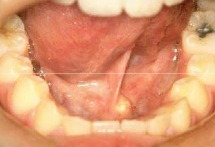

Fluid filled nodule on the floor of the mouth, usually associated with sublingual gland. Known as the "mucocele of the floor of the mouth"

Front

Ranula

Back